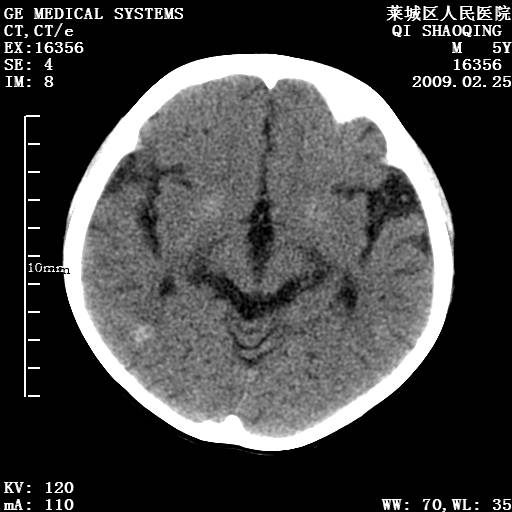

以下是引用wangzhengyuan在2009-2-28 10:22:00的发言:[br]甲状旁腺功能减退引起的脑改变.

以下是引用zsl6918在2009-2-28 10:17:00的发言:[br]首先考虑甲状旁腺功能低下所致,可结合实验室检查明确.另外需除外先天性宫内感染所致.

以下是引用余辉在2009-3-1 9:35:00的发言:[br]患者明显的肢体及智力改变,不支持fahr病,多考虑甲旁低,有可能伴有甲低(呆小症).进一步检查。